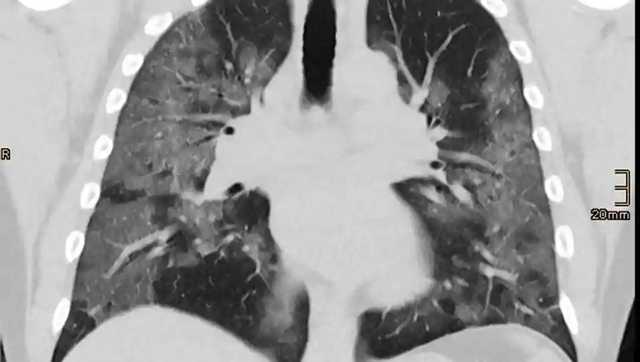

Исследования показали, что у 70% переболевших  коронавирусом людей через четыре месяца после выздоровления наблюдаются поражения внутренних органов. В исследуемой группе были молодые люди с низкой распространённостью сопутствующих заболеваний.

Через четыре месяца после инфицирования у 70% переболевших обнаружены нарушения одного или нескольких внутренних органов.

Через несколько месяцев после появления первых симптомов коронавируса у участников все еще наблюдались кардиореспираторные (92%) и желудочно-кишечные (73%) поражения, а у 42% людей было десять или более поражений различных органов, — сообщили учёные.

Исследователи утверждают, что были доказательства легкого поражения органов сердца (32%), легких (33%), почек (12%), печени (10%), поджелудочной железы (17%) и селезенки (6%).